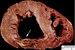

Acute myocardial infarction, reperfusion type. In this case, the infarct is diffusely hemorrhagic. There is a rupture track through the center of this posterior left ventricular transmural infarct. The mechanism of death was hemopericardium.